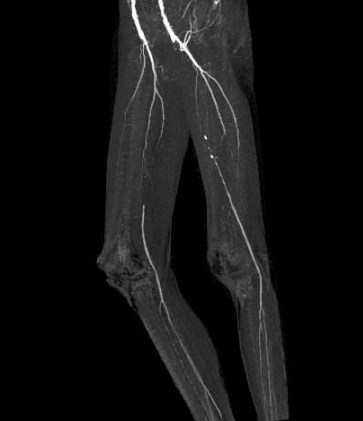

脈管炎

脈管炎症狀、原因、治療與預防保健 · 脈管炎完整疾病指南 · 脈管炎專業就醫指南

發病部位:

下肢

相關檢查:

X線片、多普勒超聲

脈管炎圖片